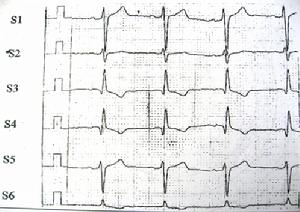

圖一 正常右側面心電圖

右側面導聯的命名可將肢體導聯的名稱前均加上“S”,即SI、SII、SIII、SaVR、SaVL、SaVF導聯;亦可與黃宛教授提出的“F導聯和V導聯”相呼應,而將右側面導聯稱為“S”導聯,各導聯依次稱為S1、S2、S3、S4、S5、S6。

右側面導聯是肢體導聯向右旋轉90°的導聯,故其心電圖的時限(間期)、P波和T波高(深)度與肢體導聯心電圖相同;右側面導聯將雙極導聯和單極加壓導聯的電極,置於胸壁前後,構成了半直接導聯,故QRS波群電壓較肢體導聯為高(圖1)。正常右側面導聯心電圖的形態:根據102例正常十二導聯心電圖的右側面導聯心電圖統計,①S1導聯的P波可直立或低平,QRS波群呈rS、Rs或RS形,T波可直立、低平、倒置或雙向;②S2導聯的P波直立或低平,QRS波群呈Rs、RS、rs或rS形,T波直立或低平;③S3導聯的P波可直立、低平或倒置,QRS波群呈qR或qr形,T波可直立、低平或倒置;④S4導聯的P波倒置,QRS波群呈QR、Qr、qR或qr形,T波倒置;⑤S5導聯的P波直立或低平,QRS波群呈Rs、rS、rs或RS形,T波直立低平或倒置;⑥S6導聯的P波可直立或低平,QRS波群呈R、qR或qr形,T波可直立、低平或倒置。